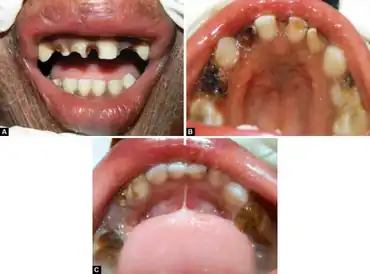

| Congenital ichthyosiform erythroderma-Dental treatment-Preoperative view: a) Maxillary anterior teeth, b) maxillary arch and c) mandibular arch | |